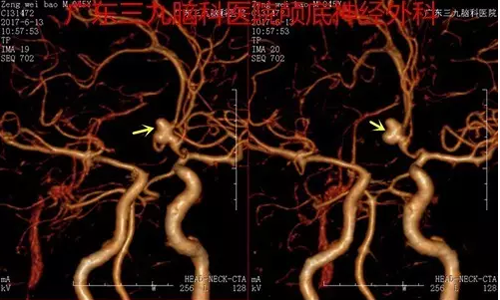

图2术前CTA提示前交通动脉示一较大不规则囊状突起,范围约9.7mm×9.3mm,瘤颈宽3mm

前交通动脉是颅内动脉瘤的高发部位,易破裂出血,其出血后致死致残率极高,早期显微手术可提高手术安全性,规避脑动脉瘤再次破裂,使致死率及致残率下降,改善患者预后。但因前交通动脉瘤位置深在,毗邻下丘脑、视交叉、垂体柄等重要结构,血管多且功能重要,动脉瘤方向多变,故手术要求高,手术难度大,术后可能出现发热、认知障碍,严重者可出现偏瘫、昏迷等。本例术前行CTA及DSA检查且结果吻合,提示前交通动脉示一较大不规则囊状突起,范围约9.7mm×9.3mm,瘤颈宽3mm。完善检查后早期行动脉瘤夹闭,术程顺利,术中尽量减少出血,阻断后予迅速夹闭,准确有效,减少缺血时间,术后患者恢复良好,术后复查DSA提示动脉瘤夹形态稳定,前交通动脉通畅。